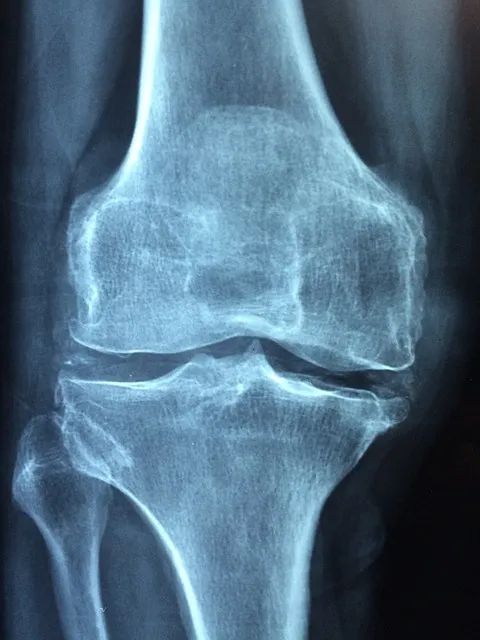

骨关节炎(OA)是另一类常见于老年人的退行性关节疾病,其特征是关节软骨的磨损和退化。关节肿胀与骨质增生是骨关节炎的常见体征。虽然OA主要影响机械性活动,但其长期炎症也可能引起类似于RA的症状,尤其是在老年患者中。